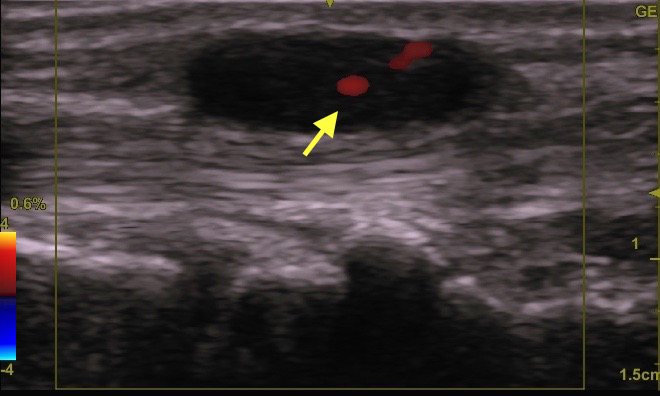

下写真のケースでは、下部に少し赤い所(→)がありますね。

エコーで見ると袋が大きく破れていました(点線部分)

こうなると、くり抜き術は難しい。

大きく切除することは可能ですが、大きな傷が残ります。

女性の首ですからね。